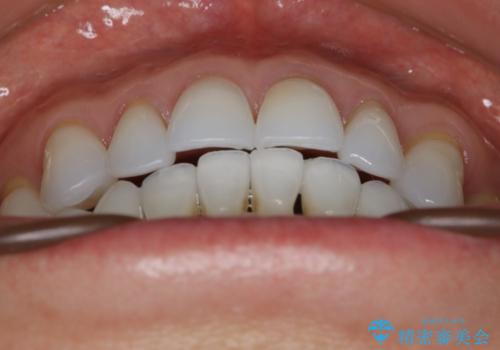

- 歯ぎしりや食いしばり、噛み合わせの治療とガタつきを治したいとのことでご来院されました。

検査の結果、前歯と臼歯の高さに差があり、前歯が全く当たらない状態になっているため歯ぎしりによって奥歯が削れてしまっているという状態でした。

マウスピースの矯正装置を用い、ガタつきを治しつつ奥歯を沈めていくことで噛み合わせ全体の改善を図りました。

オープンバイト

噛み合わせや筋機能など様々な原因で前歯の噛み合わせが大きく開いている状態を開咬(オープンバイト)といいます。

原因の除去や歯牙の移動で噛み合わせの治療を行うことで改善できる場合があります。